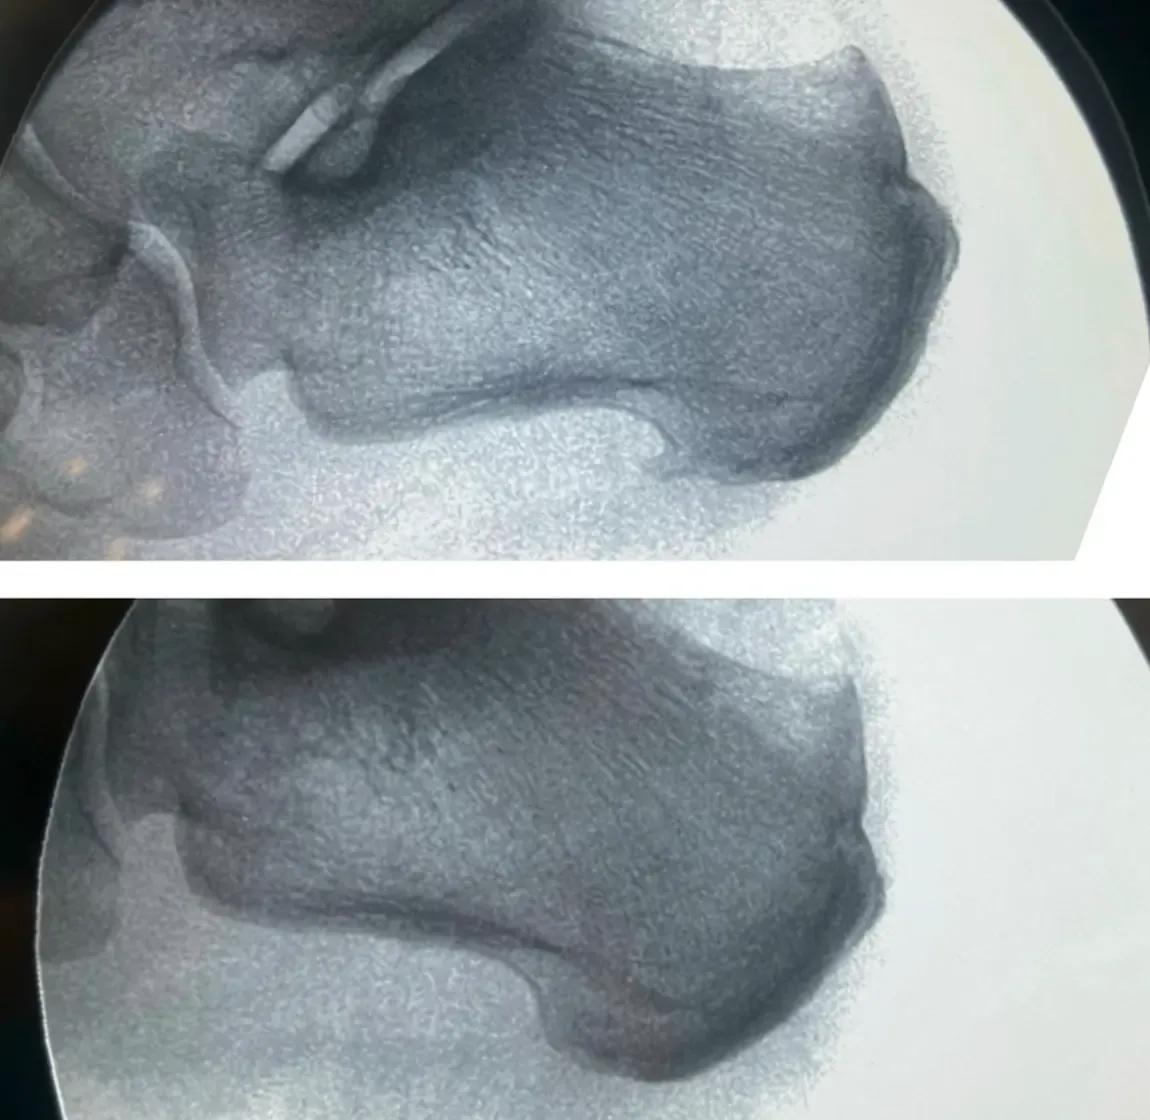

La Radiografía que lo Complicó Todo

Como muchos pacientes con dolor de talón, María acudió primero a otro profesional que le realizó una radiografía. Y ahí estaba: un espolón calcáneo visible como una pequeña espícula ósea.

“El espolón es lo que me está matando, ¿verdad? Por eso me duele tanto”, preguntó esperando confirmación.

María llegó a nuestro Centro Podológico Henao convencida de que el espolón era el culpable. Había incluso buscado en internet sobre “cirugía de espolón calcáneo”. Pero nosotros teníamos nuestras dudas.

Las radiografías muestran huesos, pero no pueden ver tejidos blandos como bursas o tendones. Por eso la ecografía podológica es fundamental en estos casos.

- El espolón calcáneo visible: presente, sí, pero sin signos inflamatorios alrededor, como un espectador silencioso

¿Y el espolón? Seguía ahí, en su radiografía. Pero María ya ni se acordaba de él.

- El espolón calcáneo raramente es la causa directa del dolor. En el caso de María, era un hallazgo radiológico incidental que distrajo la atención del verdadero problema.